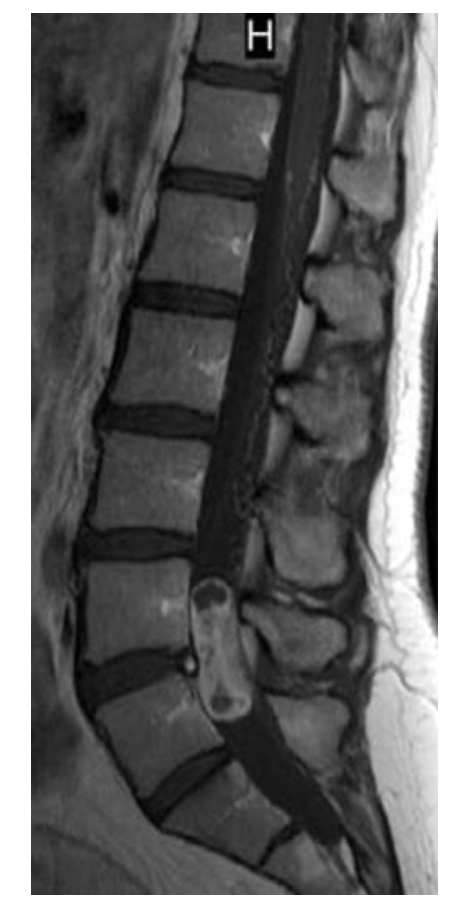

A 31-year-old man presents with back pain and erectile dysfunction. MRI is performed. Which one of the following statements regarding further management is key?

b. Craniospinal axis MRI should be performed

Myxopapillary ependymomas are most commonly benign and localize most often to the filum termi- nale and conus medullaris. They differ from other ependymomas morphologically and biologically and often resemble chordomas or chondrosarco- mas; immunohistochemical analysis is frequently required for differentiation. Myxopapillary epen- dymomas manifest in younger individuals, in com- parison with cellular ependymomas, and are also more common in male patients. They display large variations in size and are associated with scalloping of the vertebral body and enlargement of the neu- ral foramina. On T1-weighted imaging, myxopa- pillary ependymomas are most often isointense or hypointense; however, in some instances, they have displayed hyperintensity on T1-weighted imaging because of hemorrhage or their mucin content. On T2-weighted imaging, these tumors are most often hyperintense. Polar cysts are also common findings in myxopapillary ependymo- mas. Myxopapillary ependymomas are low-grade tumors that typically occur in the lumbosacral

region (filum terminale), are well-differentiated, and are often encapsulated but can seed the CSF, typically with “drop metastases” at the thecal sac. Myxopapillary ependymomas often progress slowly and cause milder-than-expected neuro- logic deficits for their size. These tumors repre- sent a special variant of ependymoma found almost exclusively in the region of the filum termi- nale, although occasionally they have been found higher in the spinal cord or, rarely, in the brain. They may occur at any age, but most arise in the fourth decade. Myxopapillary ependymomas characteristically form a sausage-shaped mass in the lumbosacral region, displacing spinal nerve roots of the cauda equina. Their biologic behavior is usually benign, but because of their location they are often associated with significant compression- induced paralysis. Treatment consists of local excision, which must often be only partial because of the tumor’s location; approximately 20% recur even after complete initial resection. Metastases infiltrating the CSF and extradural space may occur, but transformation to anaplastic variants is extremely rare. Myxopapillary subtypes appear to be associated with a favorable prognosis, poten- tially because of ease of resection because of their anatomic location. Patients who are able to achieve GTR have improved outcomes and the upfront addition of radiation therapy is of ques- tionable benefit. However, one study suggests that pediatric patients with this tumor had higher recurrence rates, even in the setting of GTR, and appeared to benefit from postoperative irradi- ation. A retrospective review from the Rare Can- cer Network suggests that higher postoperative radiation dose (>50.4 Gy) for the myxopapillary subtype may be associated with improved PFS.

A 31-year-old man presents with back pain and erectile dysfunction. MRI is performed. Which one of the following statements

regarding further management is key?

b. Craniospinal axis MRI should be

performed

Myxopapillary ependymomas are most commonly

benign and localize most often to the filum terminale and conus medullaris. They differ from other ependymomas morphologically and biologically and often resemble chordomas or chondrosarcomas; immunohistochemical analysis is frequently required for differentiation. Myxopapillary ependymomas manifest in younger individuals, in comparison with cellular ependymomas, and are also more common inmale patients. They display large variations in size and are associated with scalloping of the vertebral body and enlargement of the neural foramina. On T1-weighted imaging, myxopapillary ependymomas are most often isointense or hypointense; however, in some instances, they have displayed hyperintensity on T1-weighted imaging because of hemorrhage or their mucin content. On T2-weighted imaging, these tumors are most often hyperintense. Polar cysts are also common findings in myxopapillary ependymomas. Myxopapillary ependymomas are low-grade tumors that typically occur in the lumbosacral region (filum terminale), are well-differentiated, and are often encapsulated but can seed the CSF, typically with “drop metastases” at the thecal sac. Myxopapillary ependymomas often progressslowly and cause milder-than-expected neurologic deficits for their size. These tumors represent a special variant of ependymoma found

almost exclusively in the region of the filum terminale, although occasionally they have been found higher in the spinal cord or, rarely, in the brain.

They may occur at any age, but most arise in the

fourth decade. Myxopapillary ependymomas

characteristically form a sausage-shaped mass in

the lumbosacral region, displacing spinal nerve

roots of the cauda equina. Their biologic behavior

is usually benign, but because of their location they

are often associated with significant compressioninduced paralysis. Treatment consists of local excision, which must often be only partial because of the tumor’s location; approximately 20% recur even after complete initial resection. Metastases infiltrating the CSF and extradural space may occur, but transformation to anaplastic variants is extremely rare. Myxopapillary subtypes appear to be associated with a favorable prognosis, potentially because of ease of resection because of their anatomic location. Patients who are able to achieve GTR have improved outcomes and the upfront addition of radiation therapy is of questionable benefit. However, one study suggests that pediatric patients with this tumor had higher

recurrence rates, even in the setting of GTR,

and appeared to benefit from postoperative irradiation. A retrospective review from the Rare Cancer Network suggests that higher postoperative radiation dose (>50.4 Gy) for the myxopapillary subtype may be associated with improved PFS.